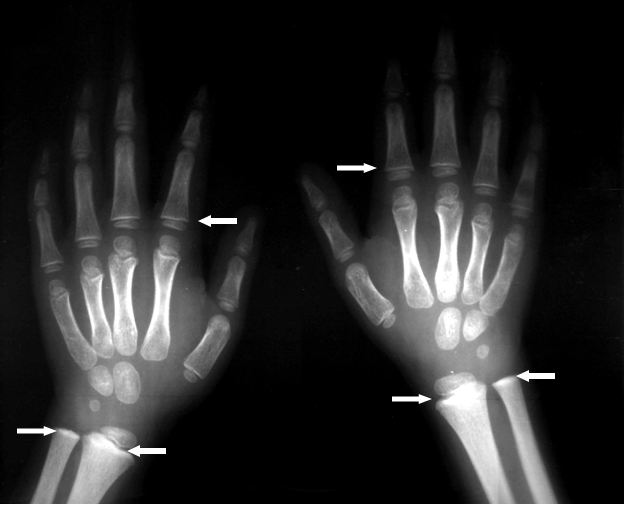

1.La opción correcta es C. La mejor prueba para confirmar la intoxicación por plomo es medir el nivel de plomo en la sangre venosa. Comentarios para la A. La mejor opción es C. La mejor prueba para confirmar la intoxicación por plomo es medir el nivel de plomo en la sangre venosa. Protoporfirina eritrocitaria (PE), comúnmente analizada como protoporfirina zinc (ZPP), no es suficientemente sensible a bajos niveles de plomo en la sangre. Comentarios para la B. La mejor opción es C. La mejor prueba para confirmar la intoxicación por plomo es medir el nivel de plomo en la sangre venosa. Las extracciones de sangre capilar pueden no ser exactas. Comentarios para la C. Correcto. La mejor prueba para confirmar la intoxicación por plomo es medir el nivel de plomo en la sangre venosa. Comentarios para la D. La mejor opción es C. La mejor prueba para confirmar la intoxicación por plomo es medir el nivel de plomo en la sangre venosa. Las radiografías abdominales pueden ser útiles en casos de altos niveles de plomo en la sangre, para descartar la ingestión de un objeto que contenga plomo. |